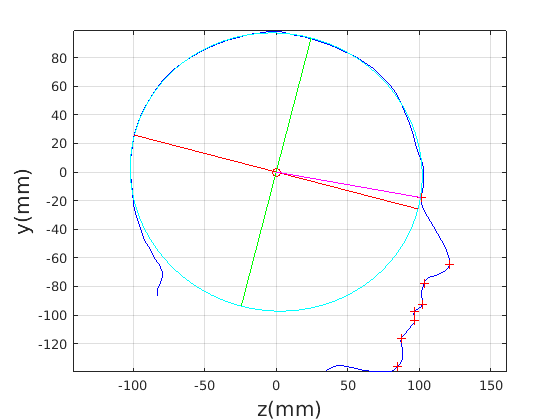

Figure 16 shows examples of the robust ellipse fit for four head profiles. The centre of the ellipse is used in a pose normalisation procedure where the ellipse centre is used as the origin of the profile and the angle from the ellipse centre to the nasion is fixed at -10 degrees. We call this Ellipse Centre - Nasion (ECN) pose normalisation and later compare this to GPA. The major and minor axes of the extracted ellipses are plotted as red and green lines respectively in Fig. 16.

|

|

|

|

Figure 17 shows all 100 profiles overlaid with the same alignment scheme. The median value of major ellipse axis and the ellipse centre-nasion angle differ by 3.6 degrees, so that when the nasion angle is fixed at -10 degrees, the median ellipse angle is -6.4 degrees (cf. -7.4 degrees with manual landmarking of the nasion). We noted regularity in the orientation of the fitted ellipse as is indicated by the clustering of the major (red) and minor (green) axes in Fig. 17 and the histogram of ellipse orientations in Fig. 18. For most people, the major axis of the ellipse is closely aligned with the y-axis (upright), and titled slightly forwards. A minority of heads (9%) in the training sample have their major ellipse axes closer to the vertical (these relatively tall and short heads are known as brachycephalic.) Ellipse axis clustering (relative to the fixed ellipse centre-nasion line) does not appear to be sharply defined. This is because many crania are close to circular in cross-section, making the orientation of these angles sensitive to small changes in shape from one person to the next. Note also the variation at the back of the head due to a variety of hair styles, some of which protrude from under the cap. We limit the region over which we model the cranial shape in order to crop this unwanted data out.